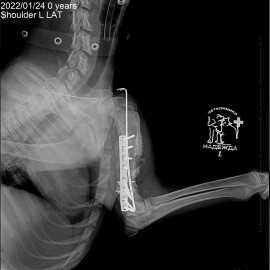

Наш пациент пёс по кличке Малыш. Обратились к нам в клинику с жалобами на хромоту на переднюю левую лапу. Был проведен осмотр и рентгенологическое исследование, после которого был поставлен диагноз: состояние после перелома левой плечевой кости. Была проведена операция: остеосинтез левой плечевой кости.

Снимок 3-4 после операции.